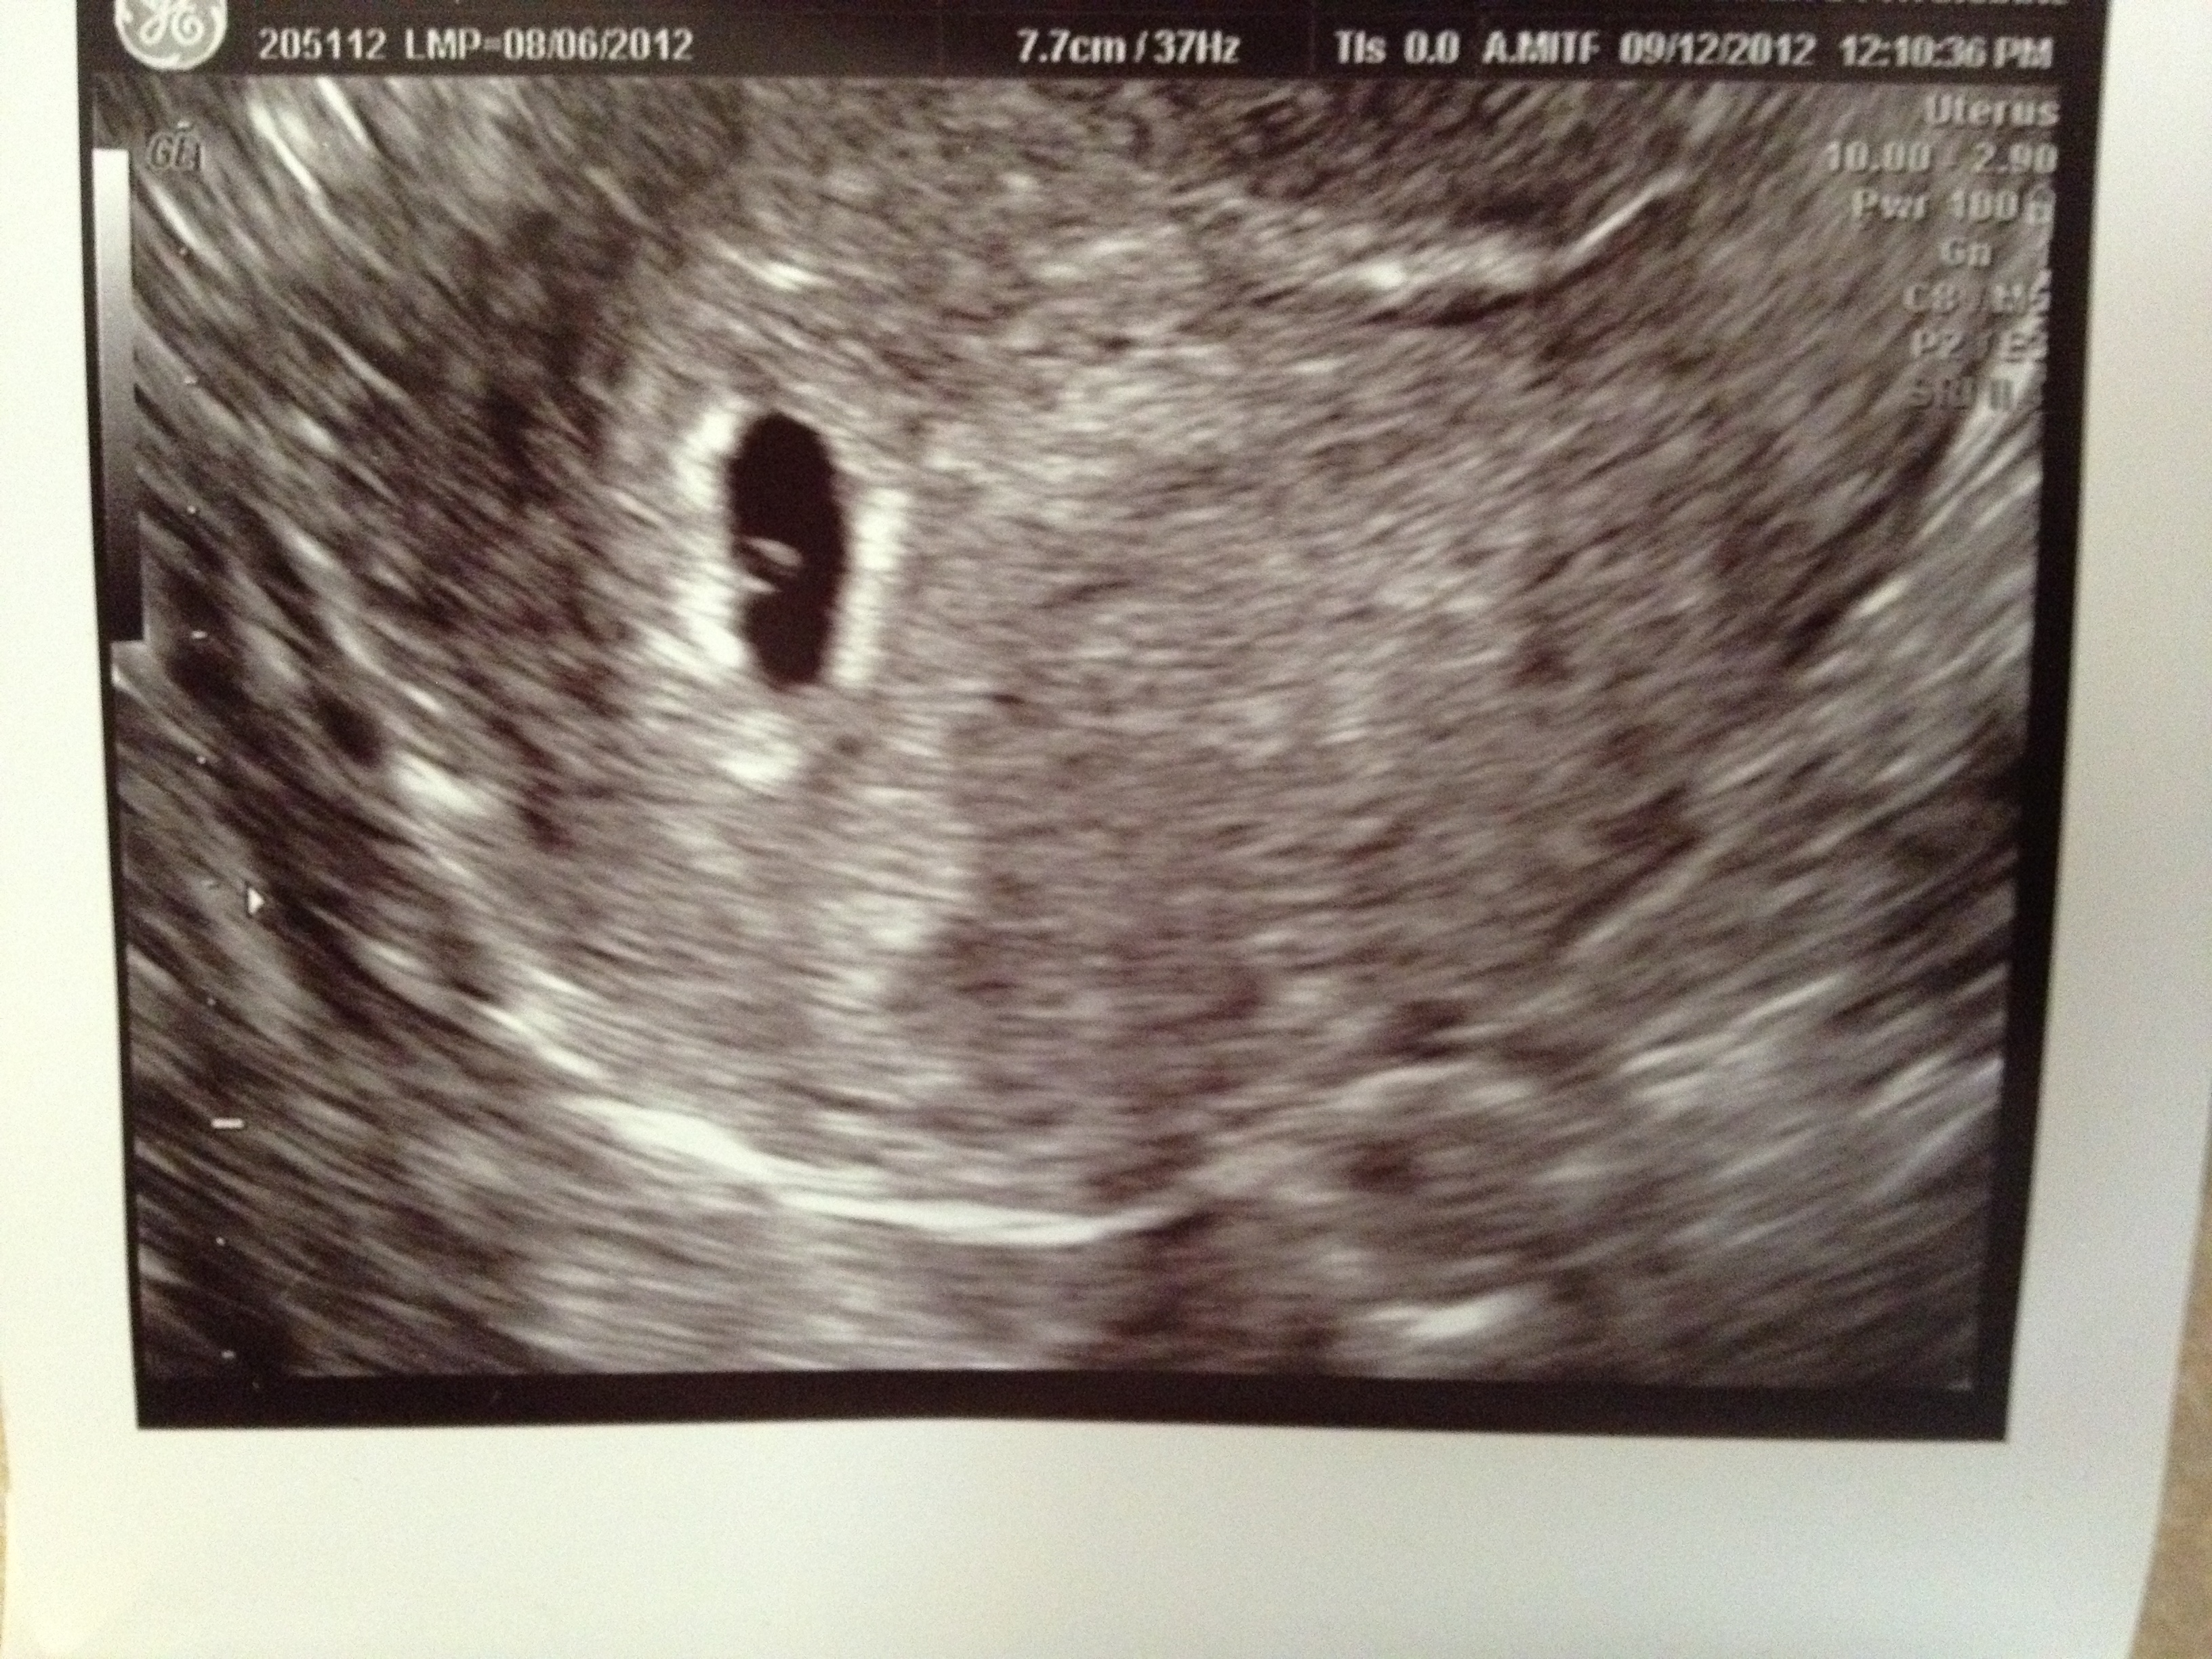

The first picture is from6 weeks 1 day the baby is on the top but hard to see), the second is earlier at 5 weeks 3 days. Both vaginal, but not sure much else.[ATTACH=CONFIG]Attachment 4675

Should say Ramzi on top. Sorry!